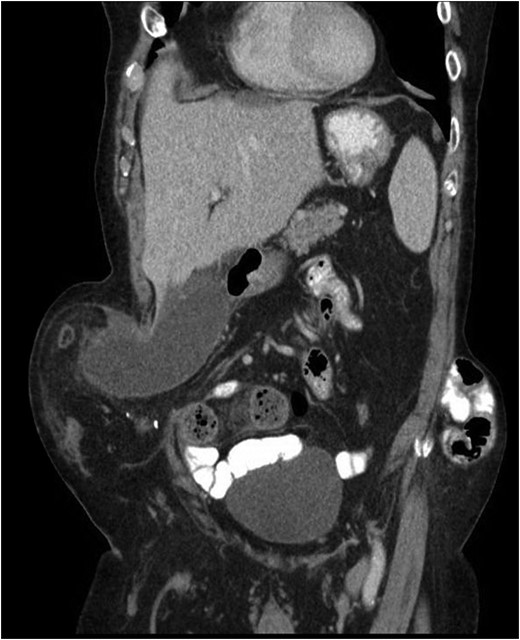

Our patient is an 89-year-old male with a history of a Hartmann’s procedure (2006) for Crohn’s disease of the sigmoid colon followed by a reversal of the colostomy with a diverting loop ileostomy (2008). Due to his comorbidities and age, the patient declined further surgery to reverse his loop ileostomy. Most recently, the patient presented to the emergency room with no ostomy output for the past 14 h, nausea and frequent burping. He reported a burning sensation around his ostomy. His physical examination revealed a large parastomal hernia in the right hemiabdomen and associated tenderness in the right upper quadrant, with no overlying skin changes. His white blood cell count was 8.1 (82.4% neutrophils), and he had normal liver function tests. A computed tomography (CT) scan of the abdomen and pelvis revealed a large parastomal hernia with a wide neck containing a distended gallbladder concerning for acute cholecystitis, as well as a small bowel obstruction with a transition point at the level of the hernia (Figs 1 and 2). A previous CT scan showed the same hernia with a nondistended gallbladder and non-obstructed bowel entering and exiting the stoma (Fig. 3).

Acute cholecystitis causing a small bowel obstruction within a parastomal hernia. Arrow points to transition point.